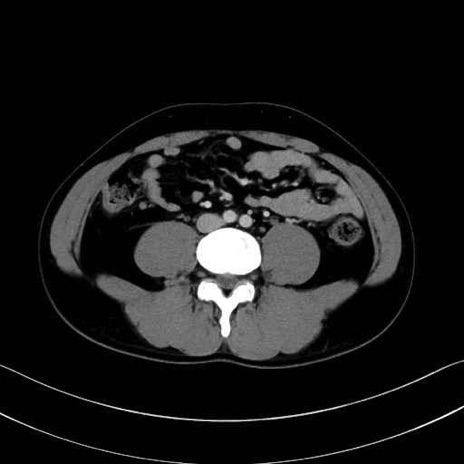

中殿筋(gluteus medius)のCT画像の解剖

症例